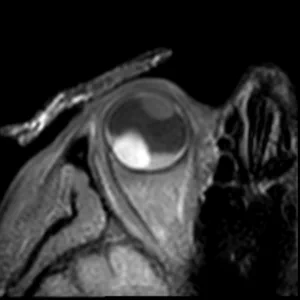

3D T1 SPIR Gd

3D T1-weighted sequence with fat supression after gadolinium contrast administration. This sequence is used to determine the enhancement pattern of the intra-ocular masses. The sequence parameters are the same as the 3D T1 SPIR sequence.